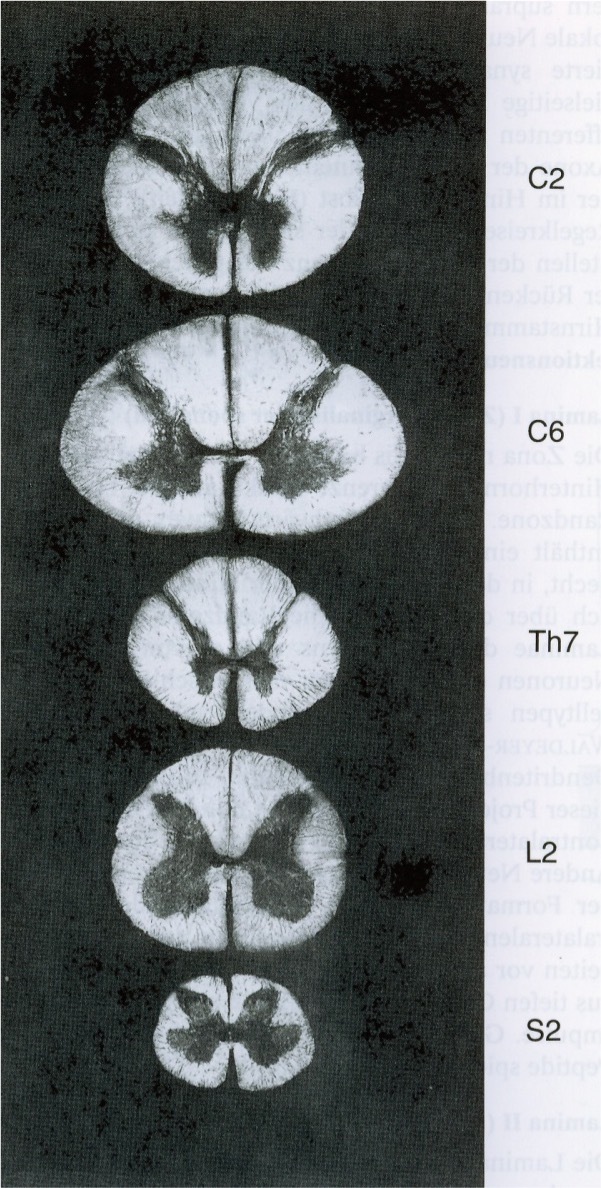

Spinal cord

White matter organized into tracts (bundles of nerve fibers with similar function)

Each tract has a defined beginning and end point

Each tract transmits a specific type of information

Ascending (cord to brain) tracts vs descending tracts (brain to effector neurons)

white and grey matter

butterfly shape grey matter

Discrimination of afferent signals in different tracts

E.g.Vibration, Temperature, Pain, Pressure

In the spinal chord, grey matter is

functionally organized

Dorsal horn

(interneurons)

ventral horn

(efferent motorneurons)

lateral horn

(cell bodies for autonomic control of cardiac and smooth muscle and glands